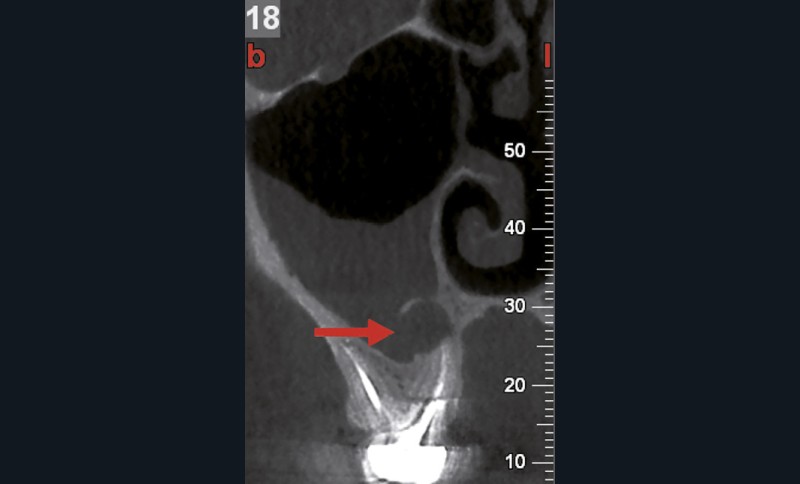

Si les isthmes sont particulièrement mis en évidence au niveau des molaires mandibulaires, cela devient médicalement important au niveau des molaires maxillaires.

La diffusion bactérienne et de leurs toxines, au niveau des molaires maxillaires est à l’origine d’un grand nombre de sinusites maxillaires chroniques, d’origine dentaire. Celles-ci sont principalement causées par l’absence de traitement du deuxième canal MV, qui existe dans 90 % des cas, et il est à noter que ces deux canaux – MV1 et MV2 – sont également reliés par un isthme.

Le nettoyage des isthmes intercanalaires reste un réel problème, et semble responsable de nombreux échecs [43]. Par ailleurs, il est nécessaire d’utiliser des instruments qui évitent de propulser les débris, tant apicalement que latéralement, en obturant les entrées isthmiques avec des débris compactés.

L’utilisation d’instruments en nickel titane, tels que le XP Shaper (FKG), le Vortex blue (Dentsply) ou le Profile (Dentsply), optimise la remontée des débris et s’inscrit dans cette nouvelle philosophie. En conséquence, la combinaison XP Shaper, XP Finisher et l’irrigation avec l’Er:YAG semblent optimiser nos traitements [44,45].

Le passage du laser est répété plusieurs fois, en début, au milieu et en fin de préparation. Un protocole peut alors être proposé : 40 mJ ; 20 Hz (fig. 7). L’utilisation de biocéramiques Bioroot (Septodont) ou Total Fill R (FKG) permet de sceller le système ainsi nettoyé, en assurant une action biologique de longue durée [46] (fig. 8a à c).